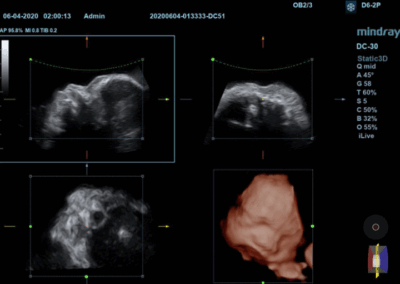

Los sistemas ecográficos estándares disponibles en la actualidad generalmente permiten un diagnóstico básico, pero carecen de funcionalidades avanzadas. Ahora, el DC-30 FullHD es la respuesta perfecta para un rendimiento de imagen de alta calidad, con una pantalla táctil de 21,5 pulgadas y funciones avanzadas como Auto IMT, iScape, elastografía Natural Touch, imágenes con contraste UWN e imágenes Doppler tisulares en el ámbito de las imágenes generales, y Smart OB, Smart face e iLive en el ámbito de la obstetricia.